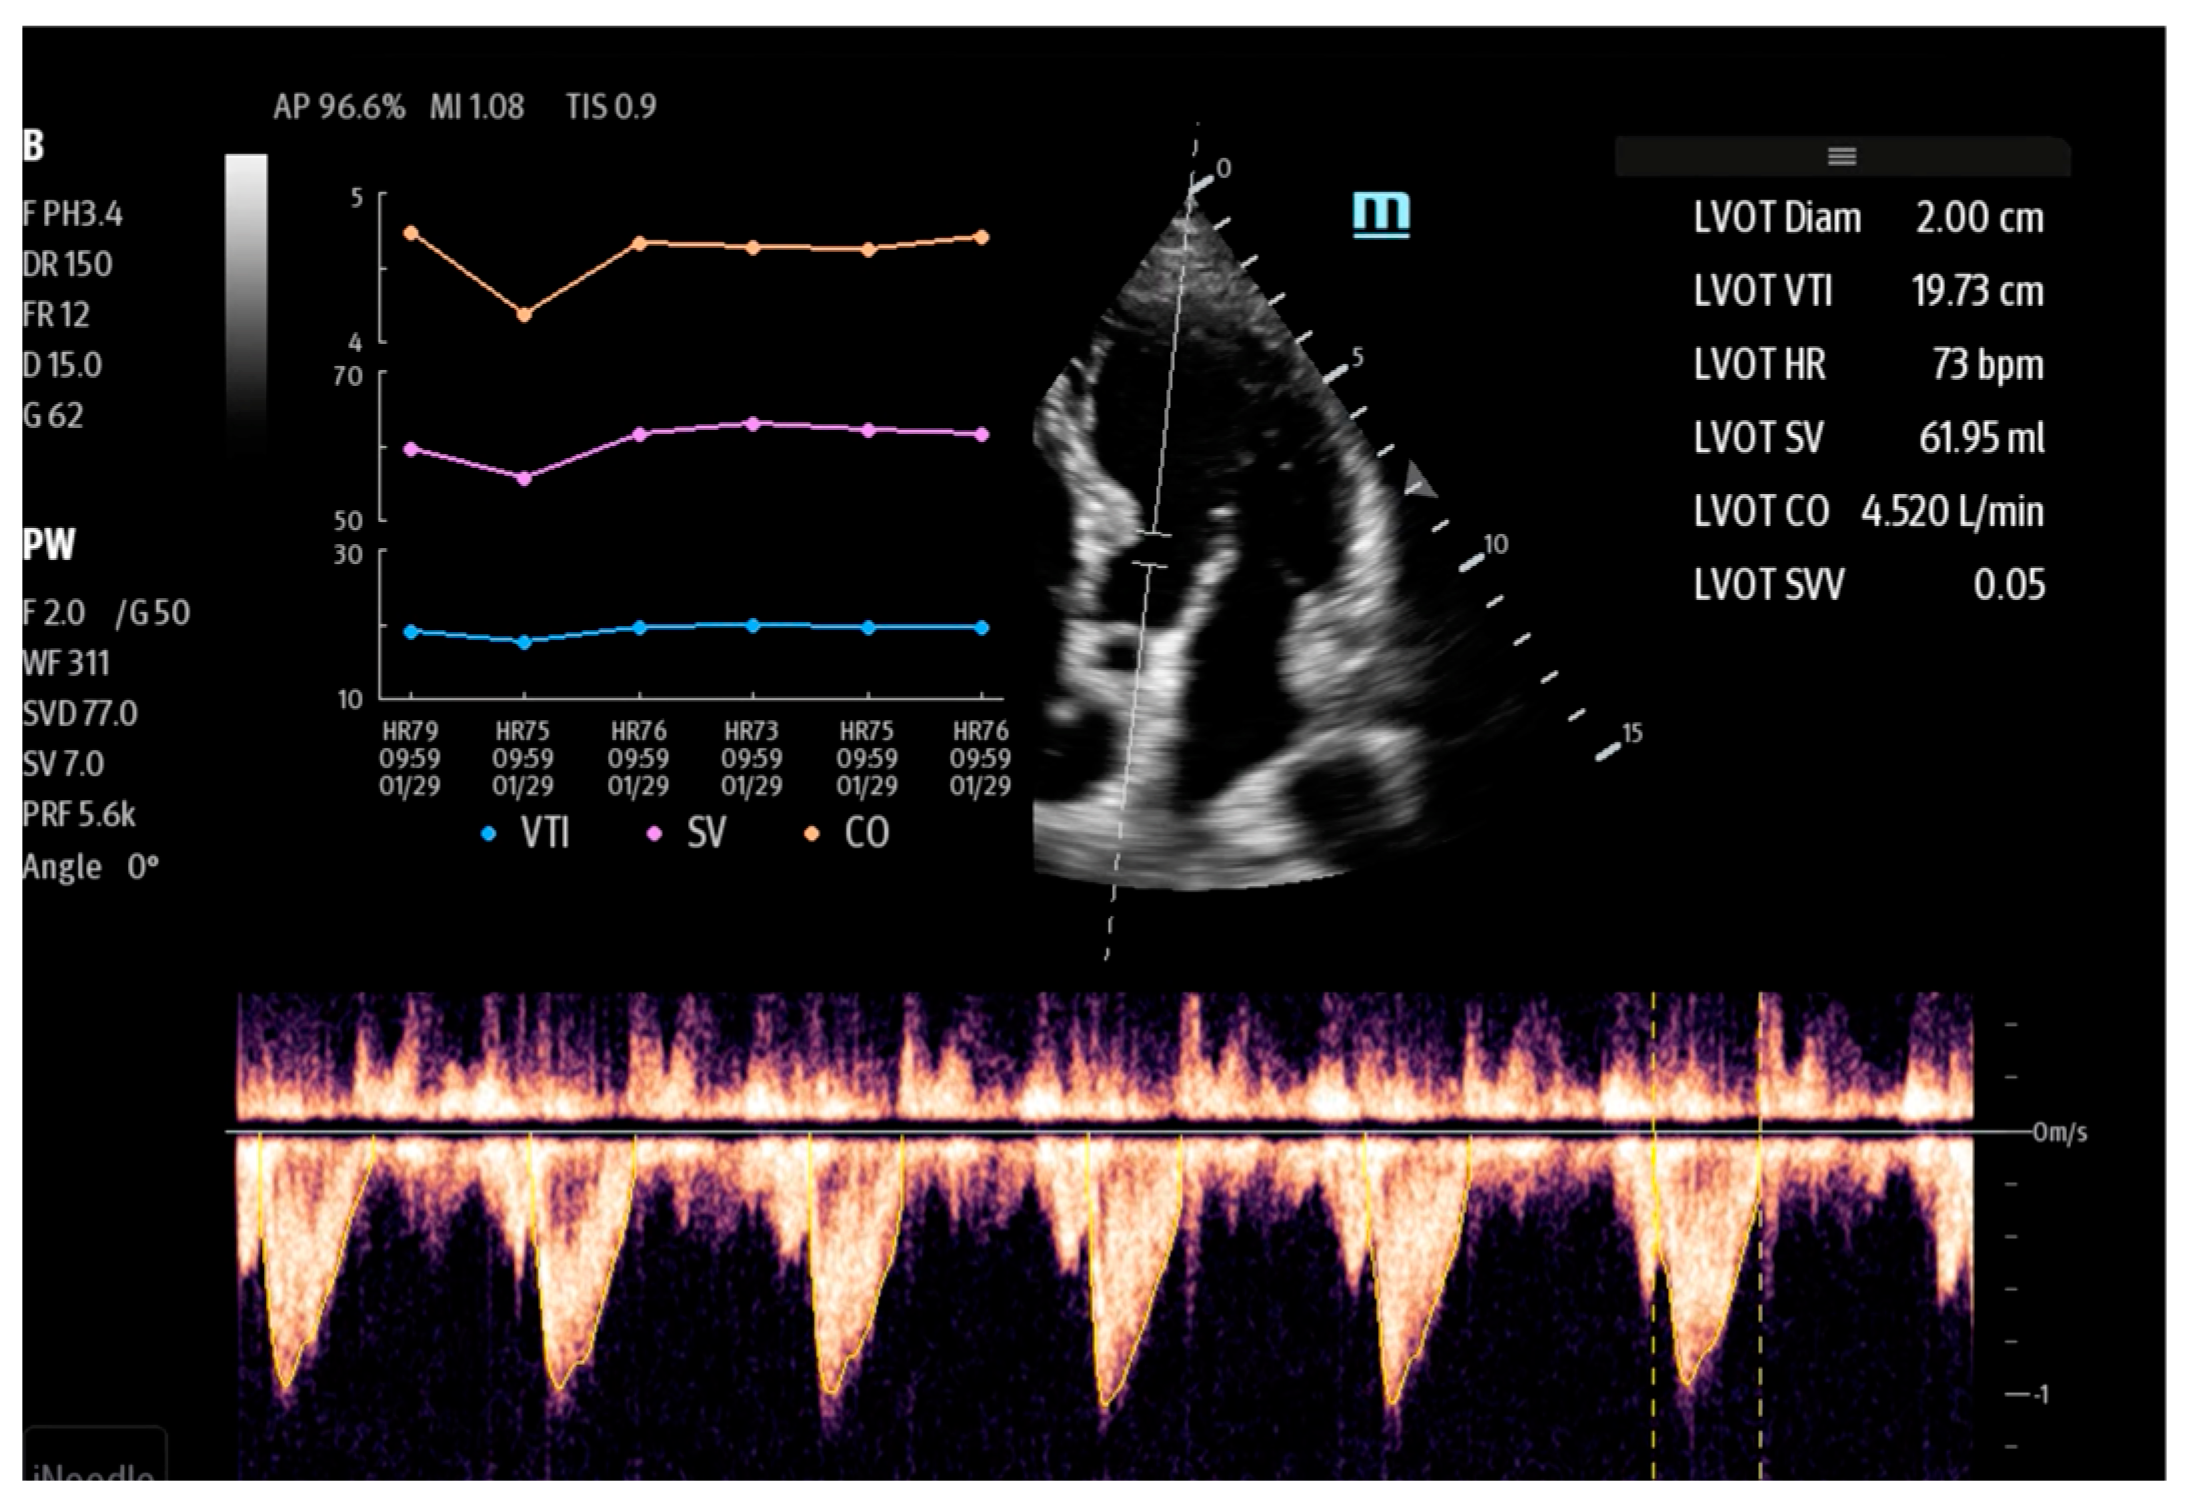

| Lvivo | Philips | automatic measurement of stroke volume (SV) and cardiac output (CO) | Ultrasonographic assessment of cardiac function |

| AutoVTI | GE | ||

| US2.AI | EchoNous | ||

| SmartVTI | Mindray | ||

- Zhai, S.; Wang, H.; Sun, L.; Zhang, B.; Huo, F.; Qiu, S.; Wu, X.; Ma, J.; Wu, Y.; Duan, J. Artificial intelligence (AI) versus expert: A comparison of left ventricular outflow tract velocity time integral (LVOT-VTI) assessment between ICU doctors and an AI tool. J. Appl. Clin. Med. Phys. 2022, 23, e13724. [Google Scholar] [CrossRef]

- Shaikh, F.; Kenny, J.E.; Awan, O.; Markovic, D.; Friedman, O.; He, T.; Singh, S.; Yan, P.; Qadir, N.; Barjaktarevic, I. Measuring the accuracy of cardiac output using POCUS: The introduction of artificial intelligence into routine care. Ultrasound J. 2022, 14, 47. [Google Scholar] [CrossRef]

- Shiran, C.; Barjaktarevic, I. VenueTM Family, Auto Tool for Measuring VTI. GE Healthcare, White Paper 2021. Available online: https://www.pocushub.net/data/venue-family_auto-vti_whitepaper_pocus__glob_jb02194xx.pdf (accessed on 1 January 2024).